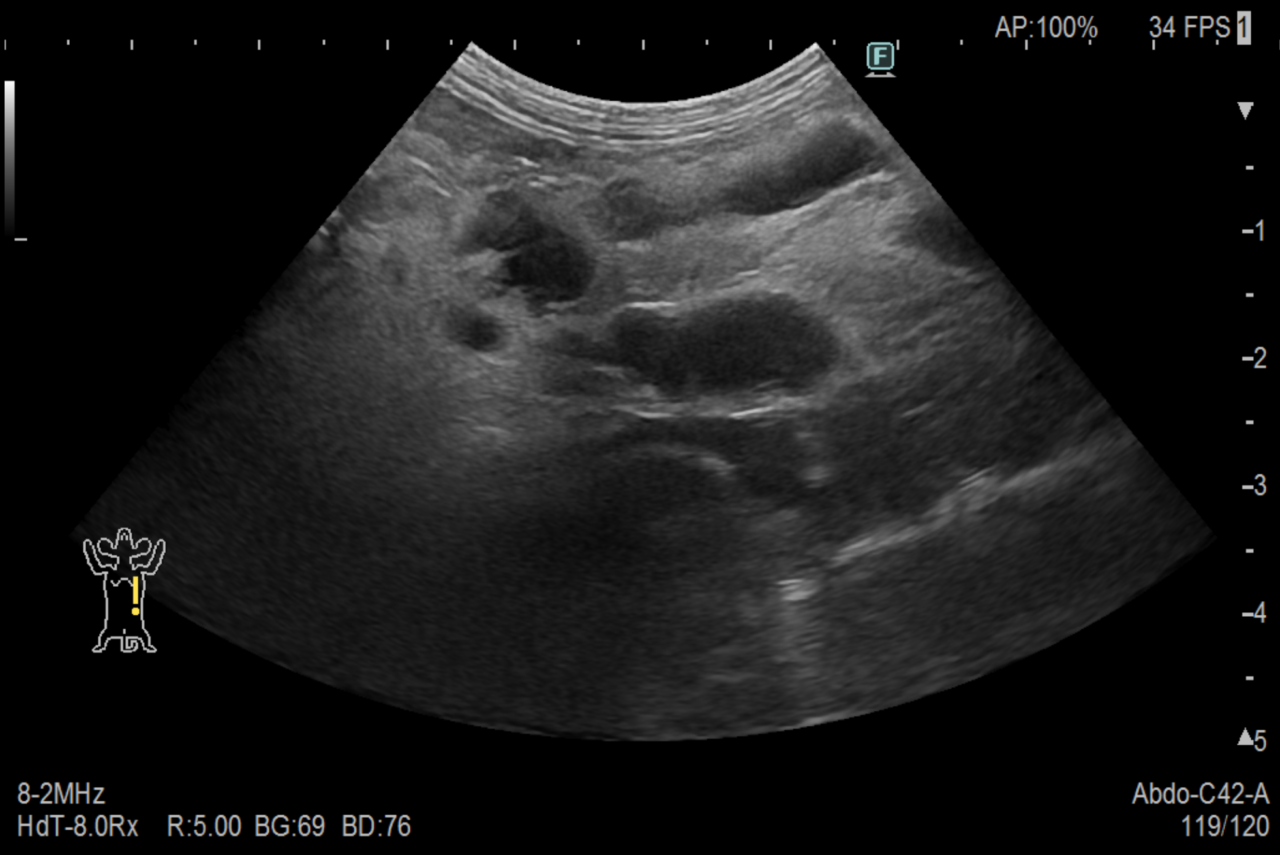

身体検査では全身のリンパ節が腫大しており、超音波検査で腹部を確認したところ重度の腹膜炎を起こしていました。